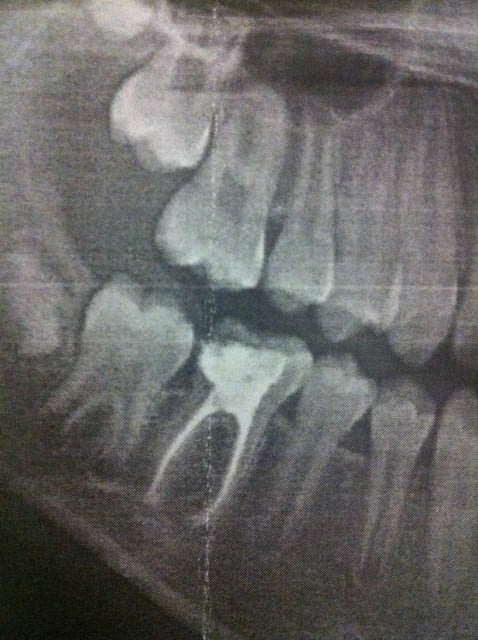

Bonjour que feriez vous sur cette 46 qui a été dépulpée correctement.

La patiente a 10 ans.

Je précise que l'image postée est pourrie car il s'agit de la fille d'une amie qui me demande conseille.

Son dentiste a refusé de lui envoyer la radio par mail et lui a donné une photocopie papier.

Le problème est que plus une dent a était dépulpée jeunes plus sa structure racinaire est faible. Cela se vois sur cette dents la canaux sont encore très large. La valeur mécanique de cette dents n'est donc pas comparable a une 6 traditionnelle.

Et la 47, qui apparemment a une grosse carie aussi (en mesial, c'est ce que je crois voir a la radio), qu'est-ce tu fais, tu l'extrais aussi?

SI une carie est confirmée et SI la vitalité ne peut être maintenue (mais avec cette radio même la présence ou non de carie est a confirmer), dans ce cas la 47 a une valeur inférieure a la 46.